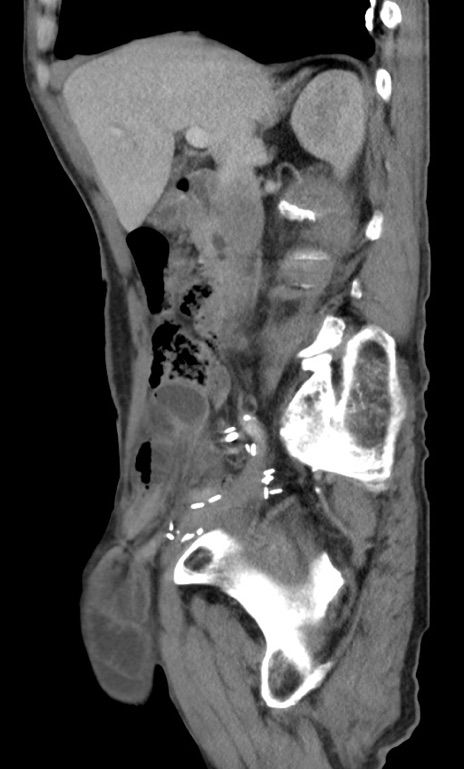

冠状断像

【症例】 70歳代男性

【主訴】右鼠径部腫瘤、疼痛

【現病歴】本日朝より上記主訴あり、受診。

【既往歴】膀胱癌にて膀胱全摘、両側尿管皮膚瘻

【データ】WBC 5600、CRP 0.56